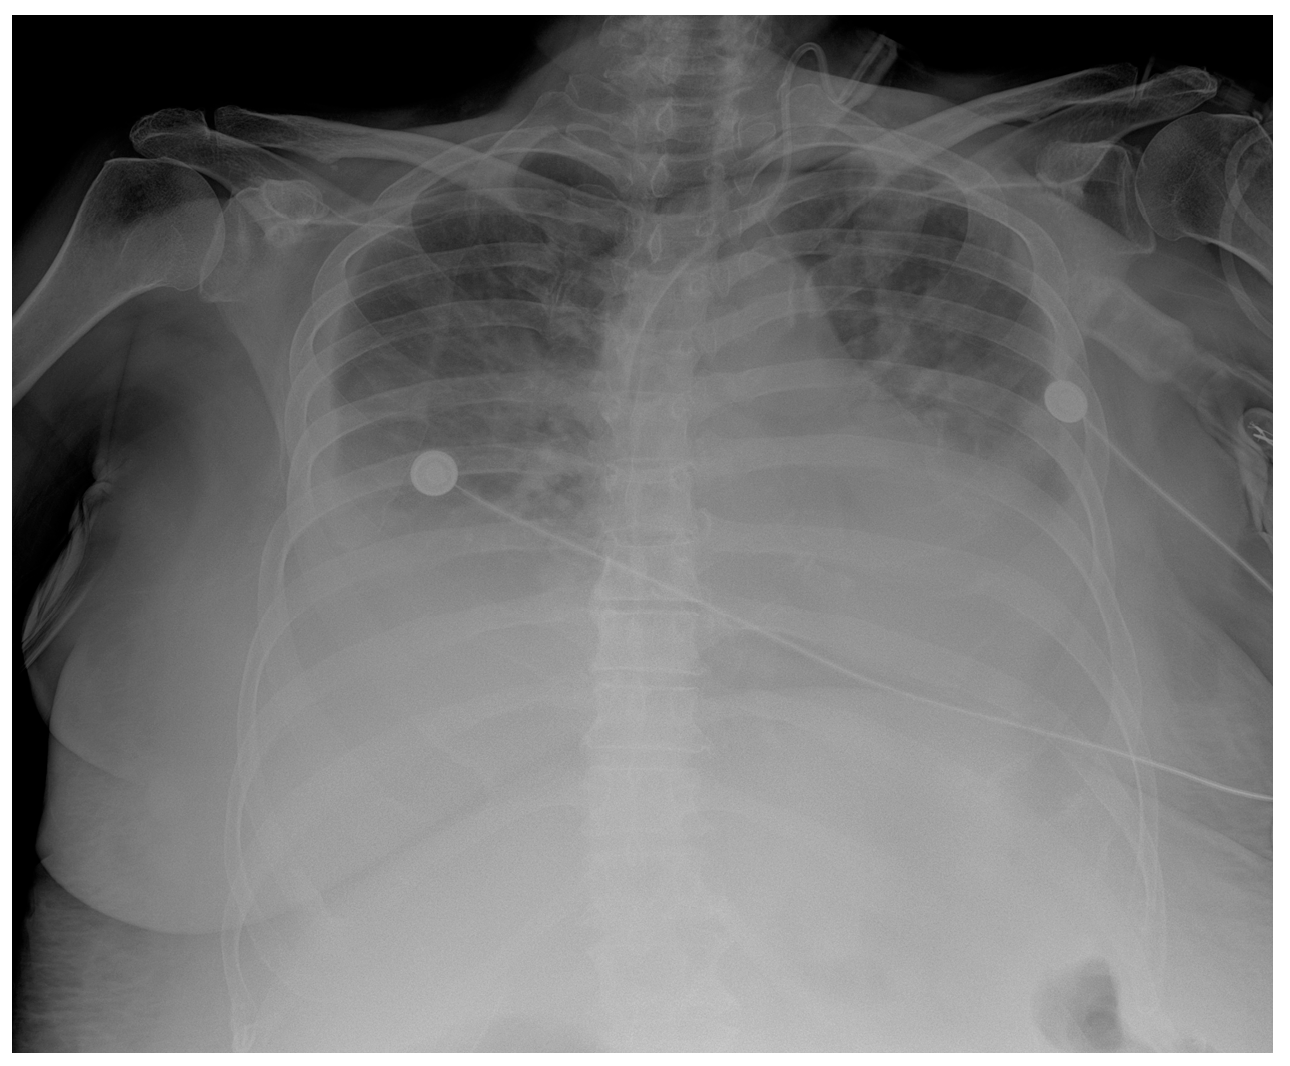

In addition, a postoperative CT scan of the chest, abdomen, and pelvis was performed. This revealed multiple focal changes in the lung, 5 to 10 mm in diameter, and a micronodular lesion of metal intensity approximately 4 mm in diameter in the middle lobe of the right lung. After the hematologist’s consultation, a bone marrow biopsy and bone marrow impression were performed. The findings of the bone marrow biopsy showed the presence of reactive bone marrow without elements of a hematologic diagnosis. Zolendronate was introduced to therapy on the 8th postoperative day by a hematologist. Respiratory support via high-flow nasal cannulae with vasopressor support using norepinephrine was initiated in the patient due to respiratory deterioration on the 9th postoperative day. The patient’s respiratory function and general condition continued to deteriorate and became fatal on the 11th postoperative day. Repeated rapid antigen and PCR tests for COVID were not positive, and the chest radiograph showed consolidation with suspected infection of SARS (Figure 5).

Figure 5.

Chest X-ray chest description—A CVC is inserted via UV in the correct position into the SVC. Upper and middle lung zones bilaterally have diffusely decreased transparency, with small discreet peripheral patchy areas of suspected consolidation COVID infection, correlating with clinical and laboratory results. Lower lung zones are bilaterally covered with a pleural effusion that fills costophrenic sinuses. The cardiac shadow is enlarged.